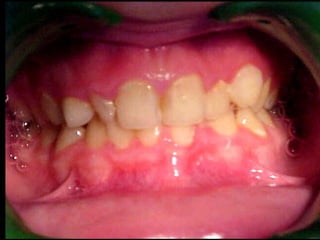

Periodontitis agresiva (de inicio precoz)

Aparece a los veinte años de edad o antes. Supone, aproximadamente, entre

un 10 y un 15% de todas las periodontitis. En la presentación clásica de la

periodontitis juvenil localizada, la pérdida ósea está localizada a los primeros

molares y a los incisivos inferiores definitivos.

Periodontitis agresiva localizada

Afecta principalmente a los primeros molares e incisivos, probablemente

porque ya están erupcionados al iniciarse la enfermedad. Puede progresar a

la forma generalizada o, posteriormente, a la periodontitis de evolución rápida.

Tanto la forma localizada como la generalizada tienen la misma etiología, pero

su presentación depende de la efectividad de la respuesta defensiva del

huésped. Existen una serie de factores asociados que son: el déficit en la

quimiotaxis de los leucocitos, el número reducido de quimiorreceptores

superficiales y la cantidad anormal de glicoproteínas en la superficie de los

Periodontitis de inicio precoz generalizada

Puede generarse desde una forma localizada o debutar así. Se distingue de la

periodontitis de evolución rápida en función del tiempo de inicio de la

enfermedad. Sin embargo, la edad no puede precisarse, pues el tiempo del

diagnóstico no coincide con el inicio de la enfermedad. Se relaciona con la

presencia de una serie de bacterias como son Aggregatibacter

actynomicetemcomitans o la Porfiromona gingivalis.

Periodontitis de inicio precoz relacionada con enfermedades sistémicas

Afecta tanto a denticiones temporales como mixtas. No suele tener un buen

pronóstico a medio y largo plazo, y supone la pérdida precoz (parcial o total) de

los dientes. Las enfermedades asociadas son: déficit de adherencia leucocitaria,

hipofosfatasia, neutropenia clínica, leucemias, sida, diabetes mellitus del tipo I,

trisomía 21, etc.